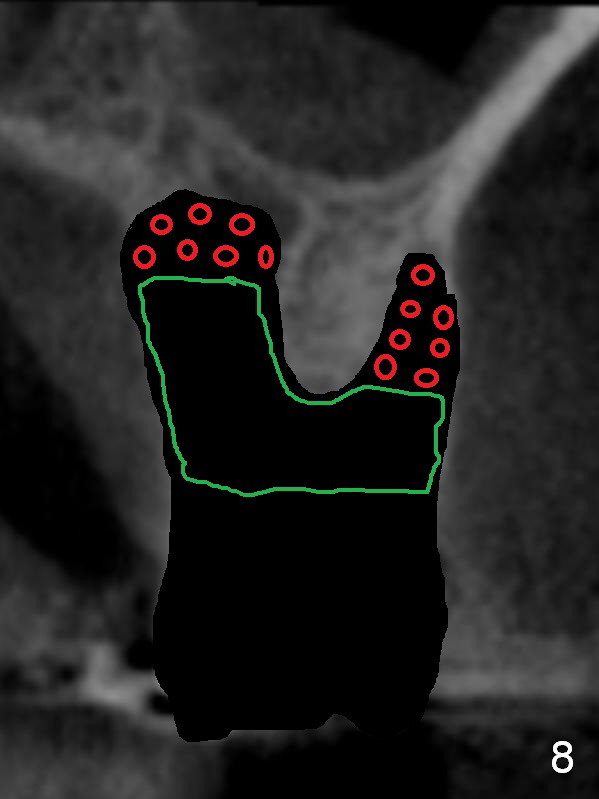

Serrated curette is used to remove granulation tissue mainly from large palatal socket, followed by copious irrigation, and placement of Clindamycin gauze x2 in the sockets. There is apical perforation of the MB socket. In the deep portion of each socket placed is ~.03 CANCELL Oss (Mineralized Cancellous Human Allograft, distributed by Impladent LTD, .850-1 mm, 03-0494763, Product Code 06412201) and equal amount of Osteogen into socket (Fig.8 red circles), covered with Osteogen plug (20x10 mm, Fig.8 green outline). The latter is fixed in placed by 4-0 Chromic gut suture (figure-8, Fig.9), followed by perio dressing, 2x2 gauze, hemastatic.